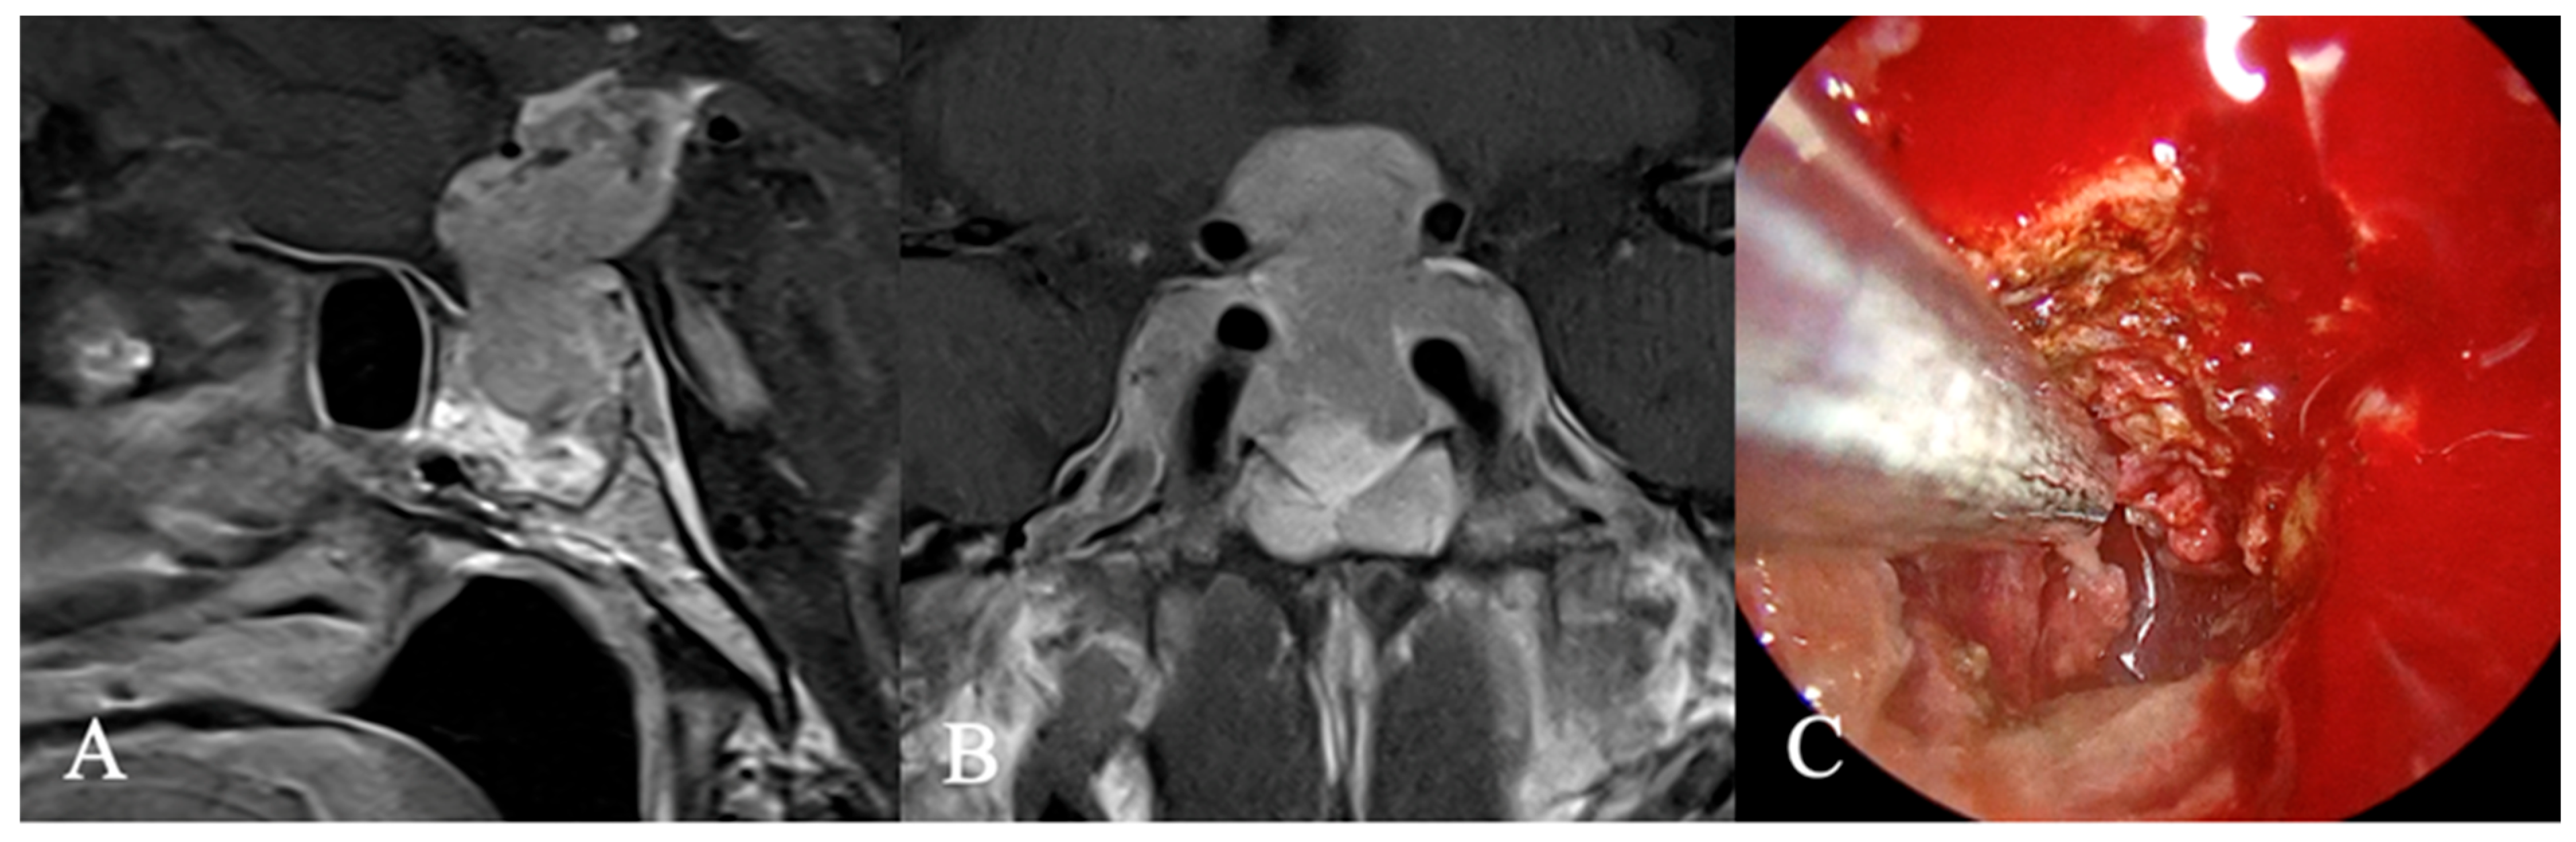

4.2. Differential Diagnoses and Case Presentations